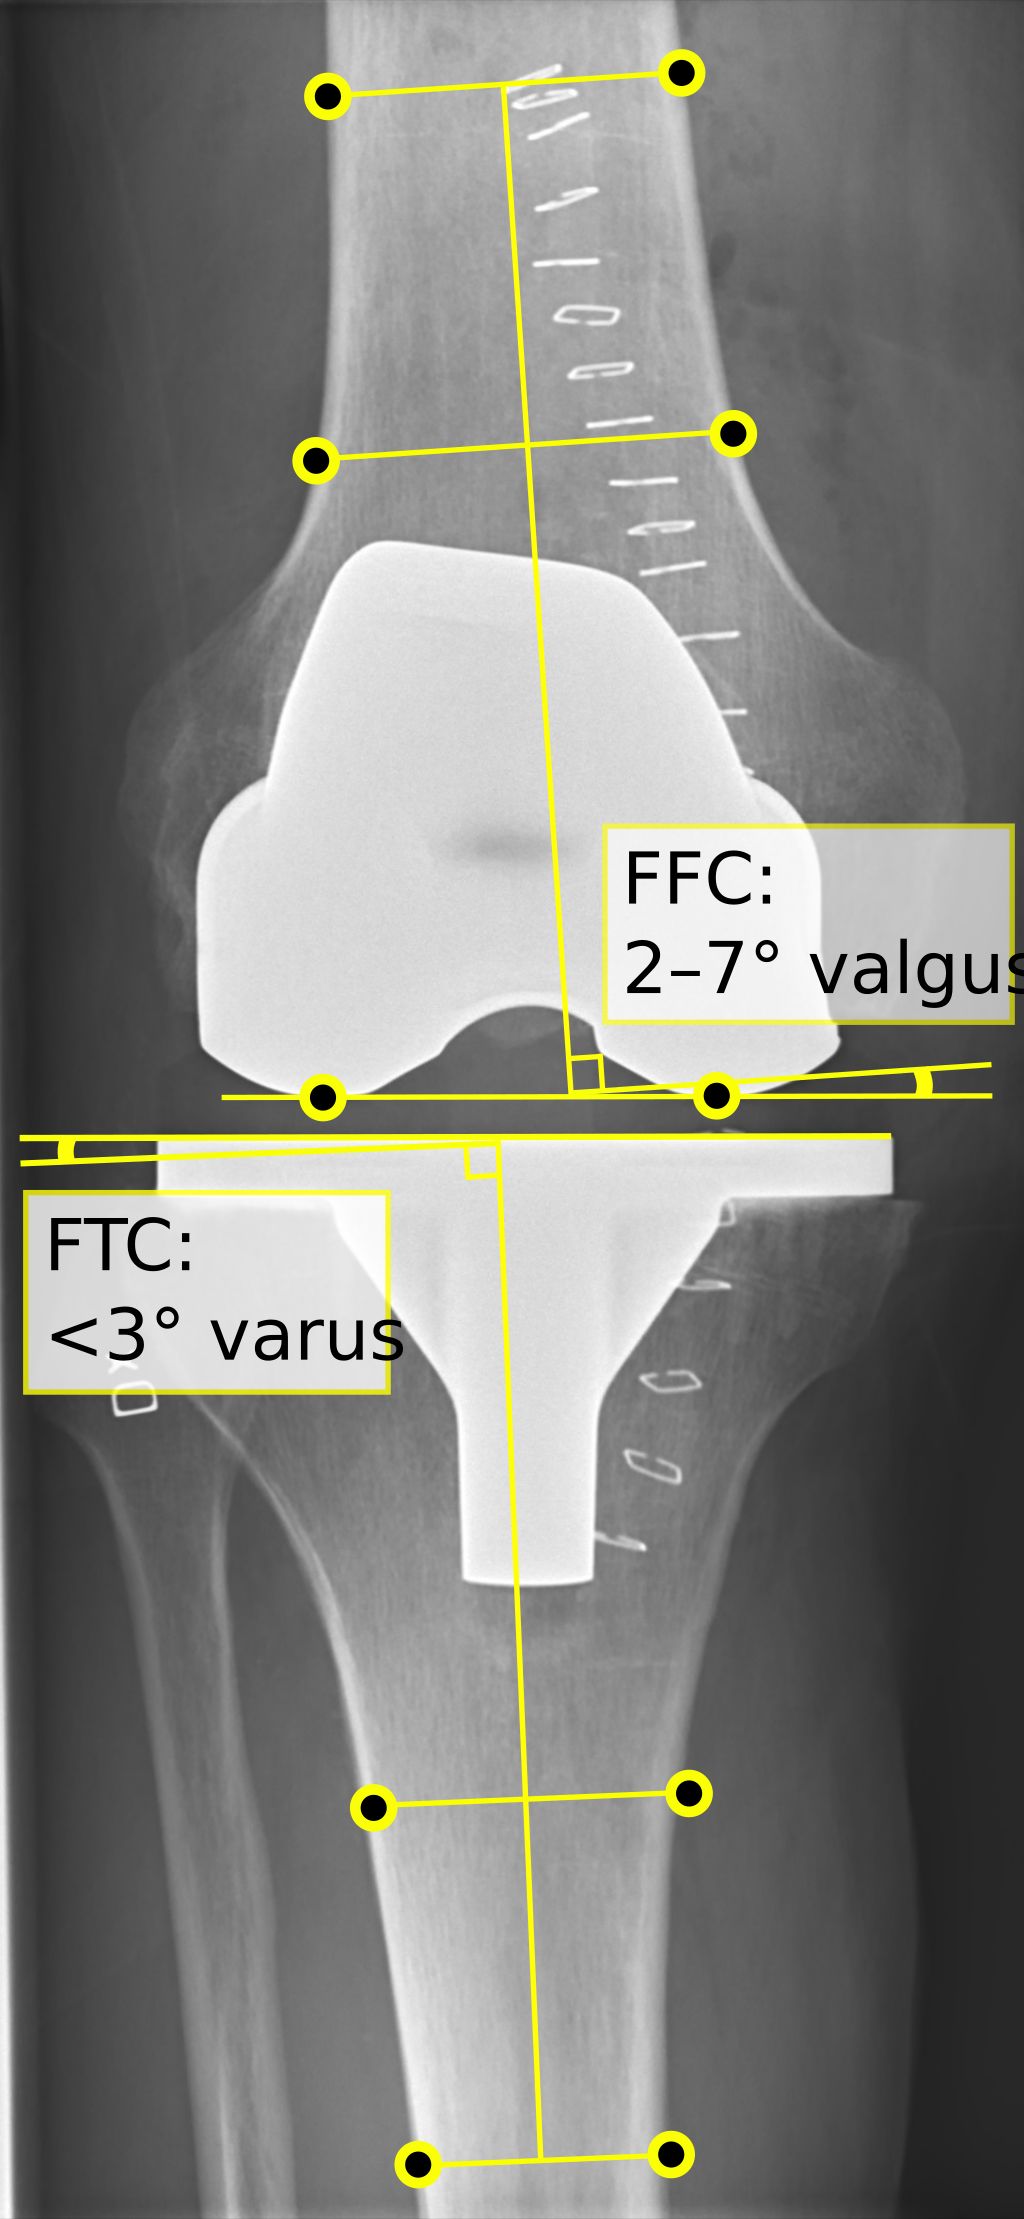

Imaging Techniques

In our quest to accurately diagnose meniscus injuries, we often turn to imaging techniques. These methods provide us with a clear picture of the internal structures of the knee, allowing us to assess the extent of the injury. Magnetic Resonance Imaging (MRI) is the gold standard for visualizing meniscus tears due to its high sensitivity and specificity. However, we also consider other modalities such as ultrasound and X-rays, particularly when MRI is contraindicated or unavailable.

Ultrasound is advantageous for its real-time imaging capabilities, which can be particularly useful in dynamic assessments. X-rays, while not as detailed for soft tissue injuries, can help rule out other conditions such as fractures or osteoarthritis. It’s important to note that while imaging provides valuable information, it should be interpreted in conjunction with clinical findings.

Tip: Always correlate imaging results with physical examination findings to ensure a comprehensive assessment of the meniscus injury.